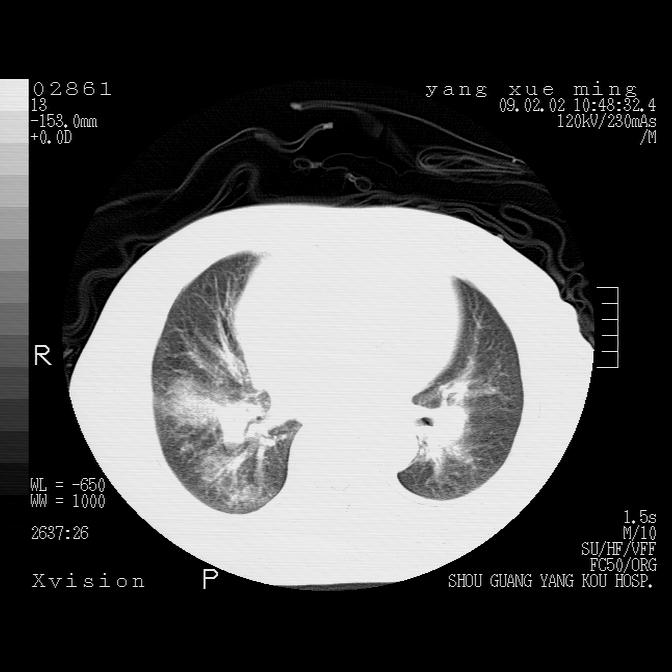

以下是引用lkc8963在2009-2-3 20:11:00的发言:[br]1)右上肺陈旧病灶。2)右下肺团块及团片影,影像表现符合感染。3)左心增大,左冠脉钙化,符合冠心病。4)双侧肺门扩大,以左侧为著,肺动脉干略粗,左上肺局限性气肿,为谨慎起见,需除肿瘤,建议增强。

以下是引用zbp537在2009-2-3 19:08:00的发言:[br]我诊断为肺泡性肺水肿。[br]诊断依据:[br]1、心影普遍增大,肺血管增粗,并见絮状高密度影,肺门改变显著。[br]2、临床上表现胸闷咳嗽,无发烧,不是一个典型的肺部感染的病史。

以下是引用王仕学在2009-2-3 20:28:00的发言:[br]考虑右下肺感染,建议治疗后复查。